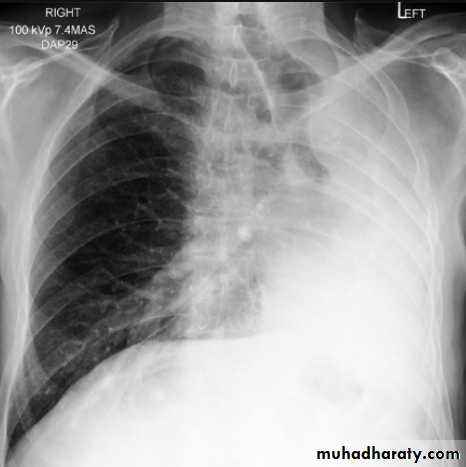

Pleural effusionPleural effusion tends to be used as a catch-all term denoting a collection of fluid within the pleural space. This can be further divided into exudates and transudates depending on the biochemical analysis of aspirated pleural fluid. Essentially it represents any pathological process which overwhelms the pleura's ability to reabsorb fluid.

Radiographic appearances

Plain radiographChest radiographs are the most commonly used examination to assess for presence of a pleural effusion, however it should be noted that on a routine erect chest x-ray as much as 250-600 ml of fluid is required before it becomes evident 6. A lateral decubitus film is most sensitive, able to identify even a small amount of fluid. At the other extreme, supine films can mask large quantities of fluid.

CXR (erect)

Both PA and AP erect films are insensitive to small amounts of fluid. Features include:

blunting of the costophrenic angle

blunting of the cardiophrenic angle

fluid within the horizontal or oblique fissures

eventually a meniscus will be seen, on frontal films seen laterally and gently sloping medially (note:

A subpulmonic effusion (infrapulmonary effusion) may be seen when there is previously established pulmonary disease, but can also be encountered in normal lungs , They are more common on the right, and usually unilateral

with large volume effusions, mediastinal shift occurs away from the effusion (note: if coexistent collapse dominates then mediastinal shift may occur towards the effusion)